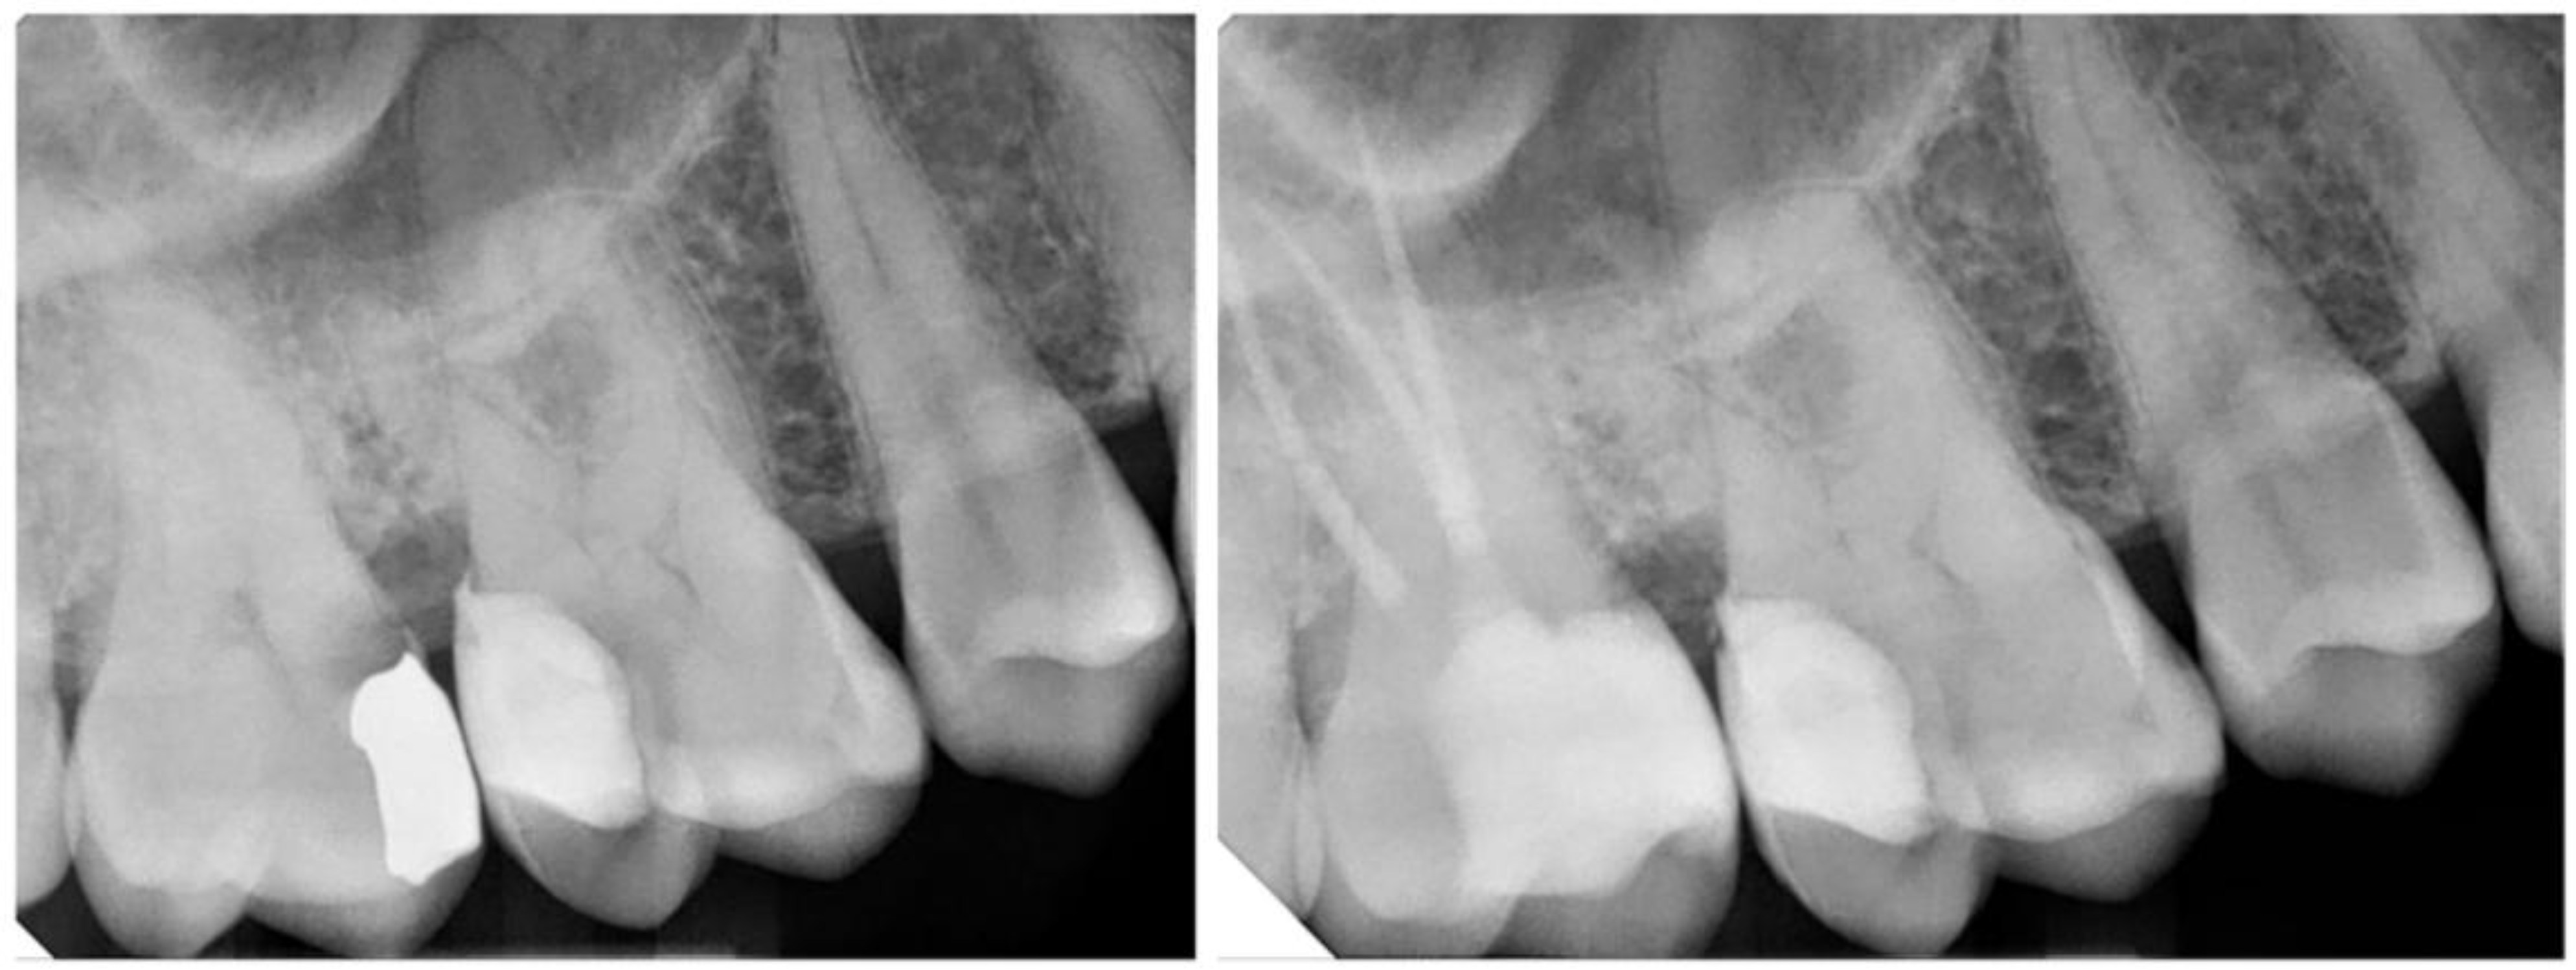

- Aziz, A.M.; Suliman, S.; Sulaiman, T.A.; Abdulmajeed, A. Clinical and Radiographical Evaluation of CAD-CAM Crowns with and without Deep Margin Elevation: 10-Year Results. J. Prosthet. Dent. 2024, in press. [Google Scholar] [CrossRef]

| 4. Aziz et al., 2024 [52] | Long-term clinical & radiographic study | DME under CAD/CAM ceramic crowns | Clinical and radiographic evaluation over 10 years | CAD-CAM crowns with vs. without DME | DME is a viable long-term option for subgingival margins in full crowns |